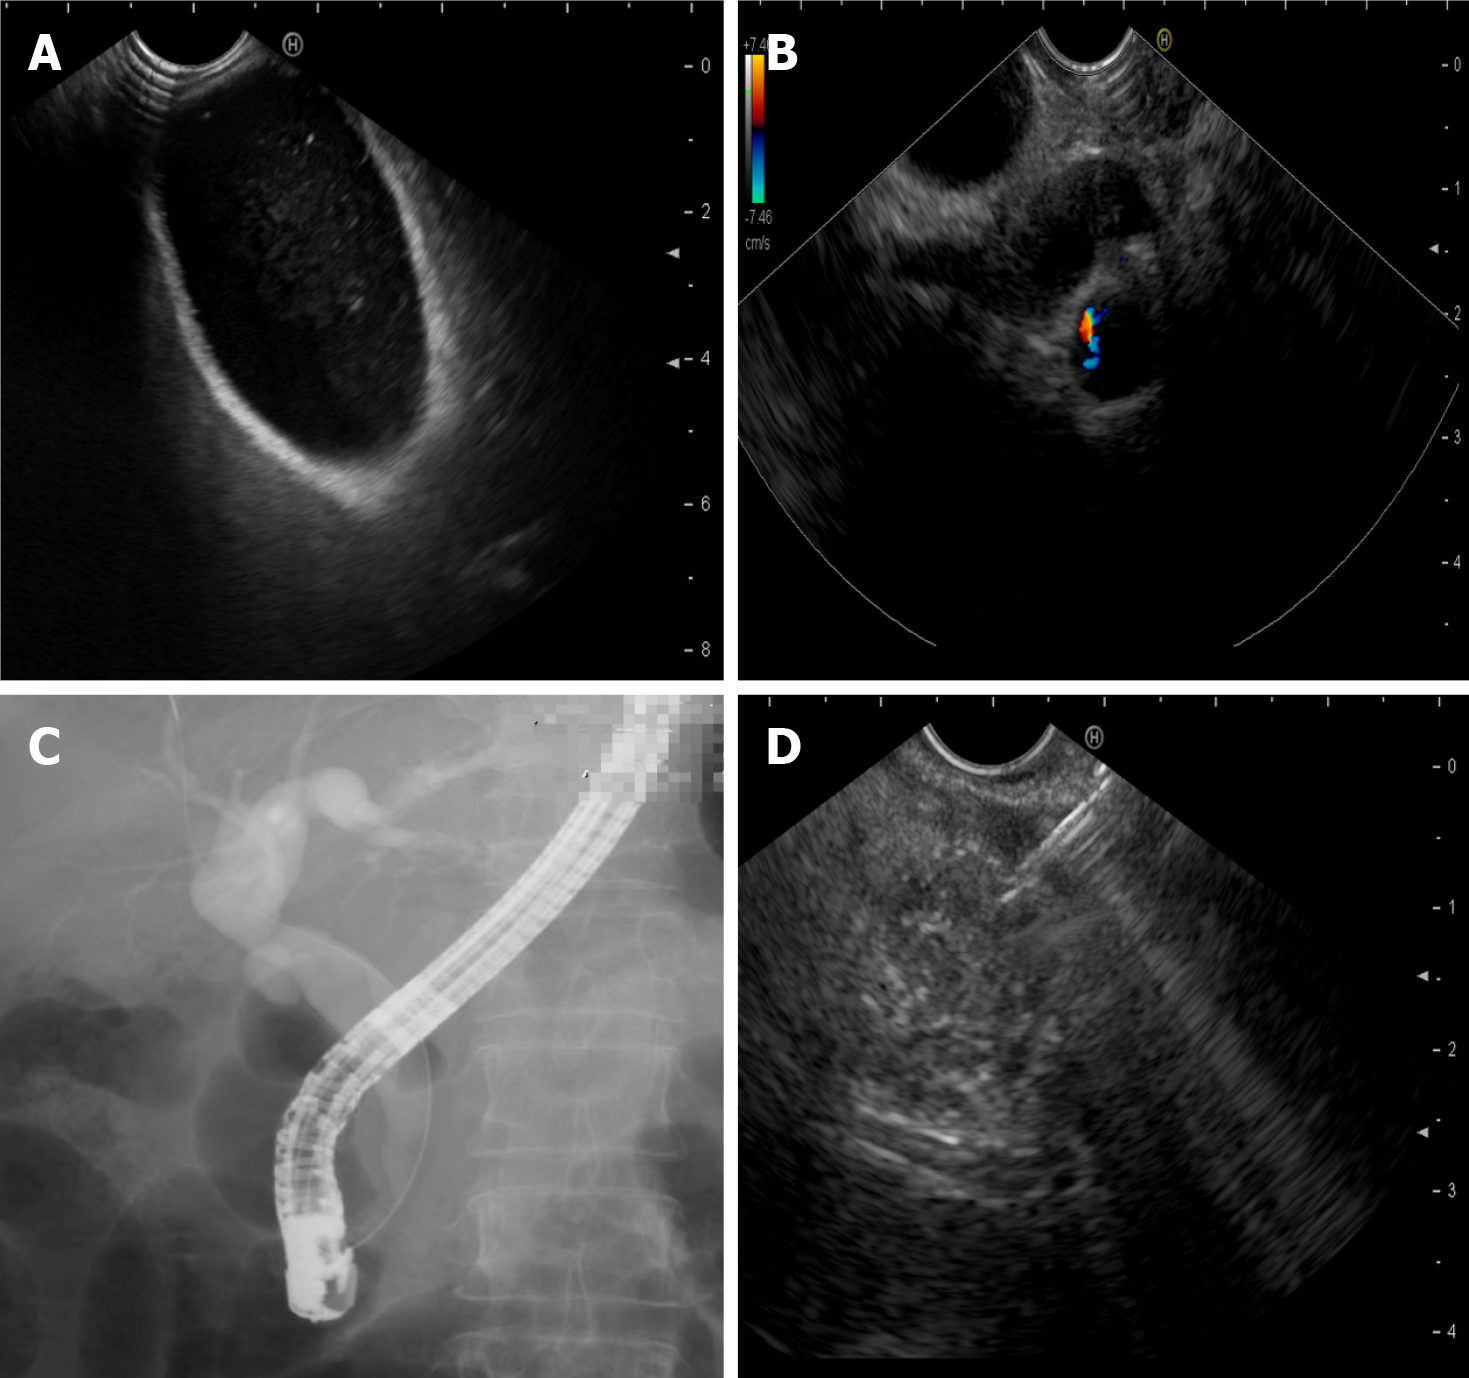

Figure 1 Endoscopically diagnosed etiology of pancreatitis.

A: Cholecystic microlithiasis detected by endoscopic ultrasound (EUS); B: Biliary sludge detected by EUS; C: Sphincter of Oddi dysfunction detected by endoscopic retrograde cholangiopancreatography; D: Small pancreatic cancer confirmed by EUS-guided fine-needle aspiration.